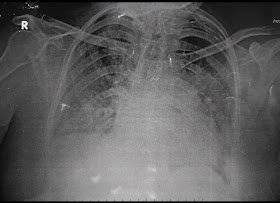

[8/7, 10:07 AM] PaJR Coordinator: We need to see her recent X-ray of lumbo sacral spine lateral view and AP view along with sacroiliac joints.

If it's done already, please share here if possible

[8/7, 10:07 AM] PaJR Coordinator: We need to see the x-ray films and not just the reports

Also please share the x-ray of her sacroiliac joints if available

[8/7, 10:07 AM] PaJR Coordinator: Wondering what those white fluffy opacities are in the pelvis! Let's hope they are artifacts but it will be very difficult to believe that till we can repeat and confirm that they were indeed artifacts!

Only the radiologist who supervised the x-ray at that time can confirm or we may need to repeat

[8/7, 10:07 AM] PaJR Coordinator: Please share the report of this x-ray! Was any medication given prior to this procedure? Medication such as barium sulfate?

[8/7, 10:07 AM] PaJR Coordinator: Appears to be a paraspinal muscular pain